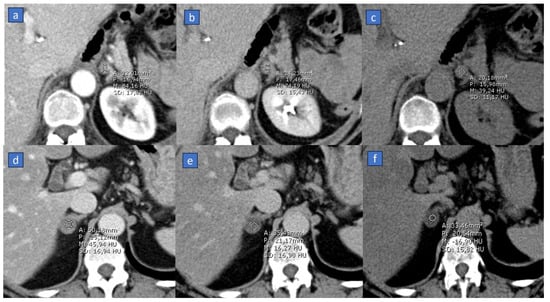

2. Virtual Non-Contrast (VNC)

Applications